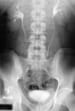

Intravenous urogram in a patient with retroperitoneal fibrosis shows medial deviation of the middle part of both ureters.